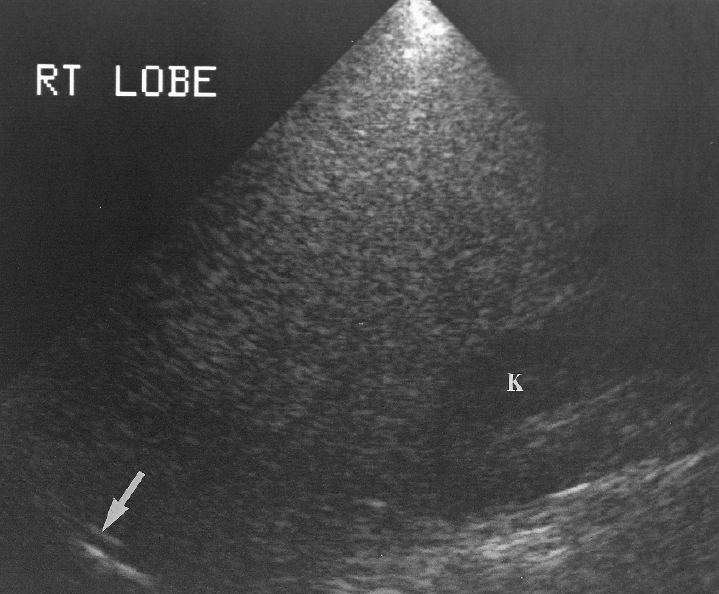

What is riedel's lobe?

congenital variant extension of the right lobe of the liver beyond the lower pole of the right kidney.

What is the major problem with riedel's lobe?

It can be mistaken for hepatomegaly

Riedel’s lobe

Absence of left lobe

Multiple sizes

Multiple shapes